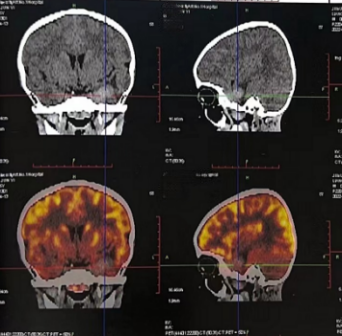

PET-CT(2022.5.12):

左侧眼眶后壁及左侧颞骨骨质破坏,伴颞面及左侧颞叶高密度影,代谢活性弥漫增高,有少量肿瘤代谢活性残余,评估为部分缓解(PR)。

头部MRI检查(2023.03.17):

左侧蝶骨大翼区及邻近颞叶未见异常强化,提示达到完全缓解(CR)。

PET-CT(2023.05.12):

颅骨、颞面及左侧颞叶高密度影消失。